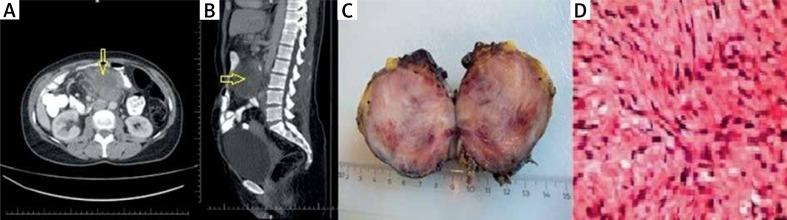

Local recurrence of sporadic mesenteric fibromatosis following radical surgery attacking the proximal jejunum.

https://cdn.ncbi.nlm.nih.gov/pmc/blobs/1280/5672713/4da627bd8493/PG-12-30734-g001.jpg